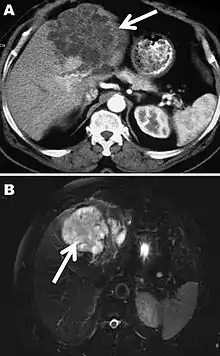

A formal diagnosis of any type of echinococcosis requires a combination of tools that involve imaging techniques, histopathology, or nucleic acid detection and serology. For cystic echinococcosis diagnosis, imaging is the main method—while serology tests (such as indirect hemagglutination, ELISA (enzyme linked immunosorbent assay), immunoblots or latex agglutination) that use antigens specific for E. granulosus verify the imaging results. The imaging technique of choice for cystic echinococcosis is ultrasonography, since it is not only able to visualize the cysts in the body's organs,[30] but it is also inexpensive, non-invasive and gives instant results.[31] In addition to ultrasonography, both MRI and CT scans can and are often used although an MRI is often preferred to CT scans when diagnosing cystic echinococcosis since it gives better visualization of liquid areas within the tissue.[30][32]

Alveolar

As with cystic echinococcosis, ultrasonography is the imaging technique of choice for alveolar echinococcosis and is usually complemented by CT scans since CT scans are able to detect the largest number of lesions and calcifications that are characteristic of alveolar echinococcosis. MRIs are also used in combination with ultrasonography though CT scans are preferred. Like cystic echinococcosis, imaging is the major method used for the diagnosis of alveolar echinococcosis while the same types of serologic tests (except now specific for E. multilocularis antigens) are used to verify the imaging results. It is also important to note that serologic tests are more valuable for the diagnosis of alveolar echinococcosis than for cystic echinococcosis since they tend to be more reliable for alveolar echinococcosis since more antigens specific for E. multilocularis are available.[19] In addition to imaging and serology, identification of E. multilocularis infection via PCR or a histological examination of a tissue biopsy from the person is another way to diagnose alveolar echinococcosis.[30]